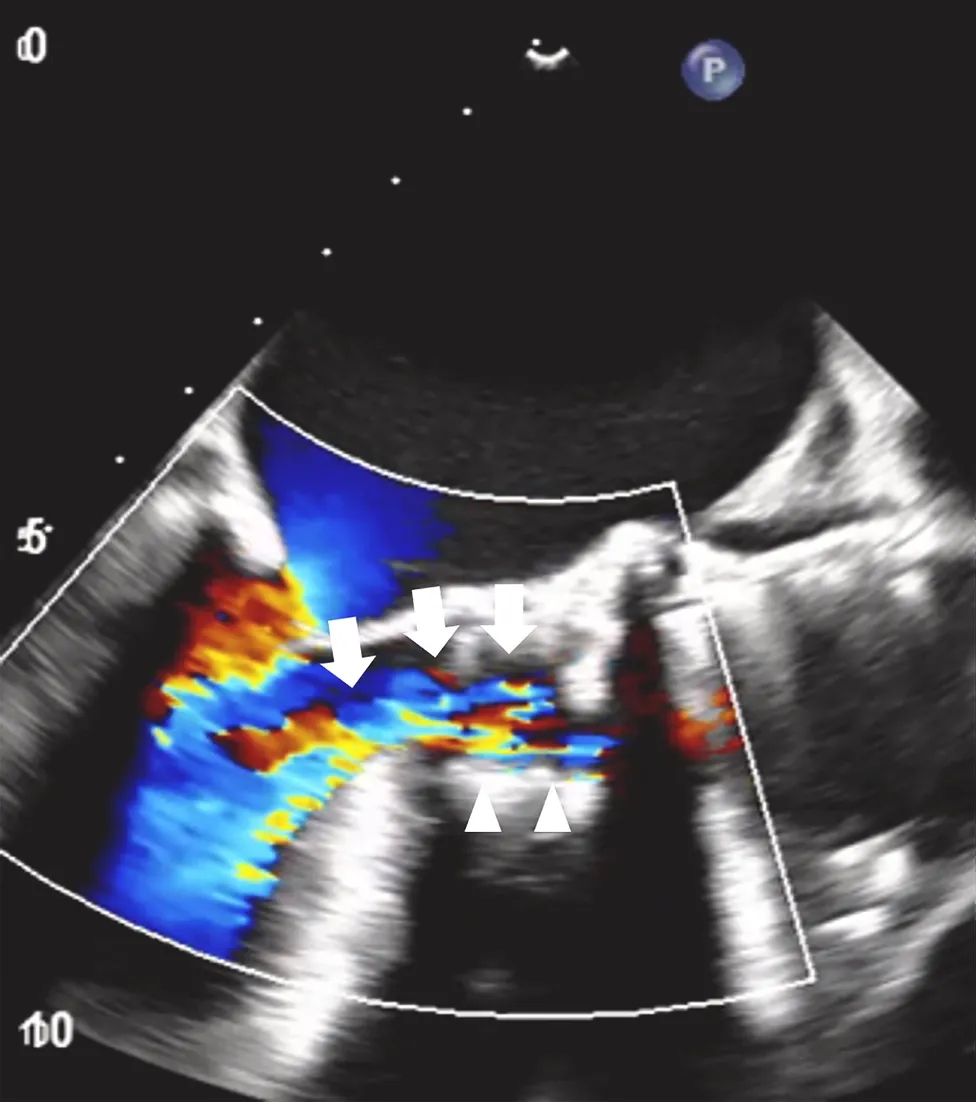

图2经食道超声心动图显示的左心室流出道视图

可见严重的跨瓣膜反流(白色箭头),以及轻微的瓣周反流(白色箭头)。